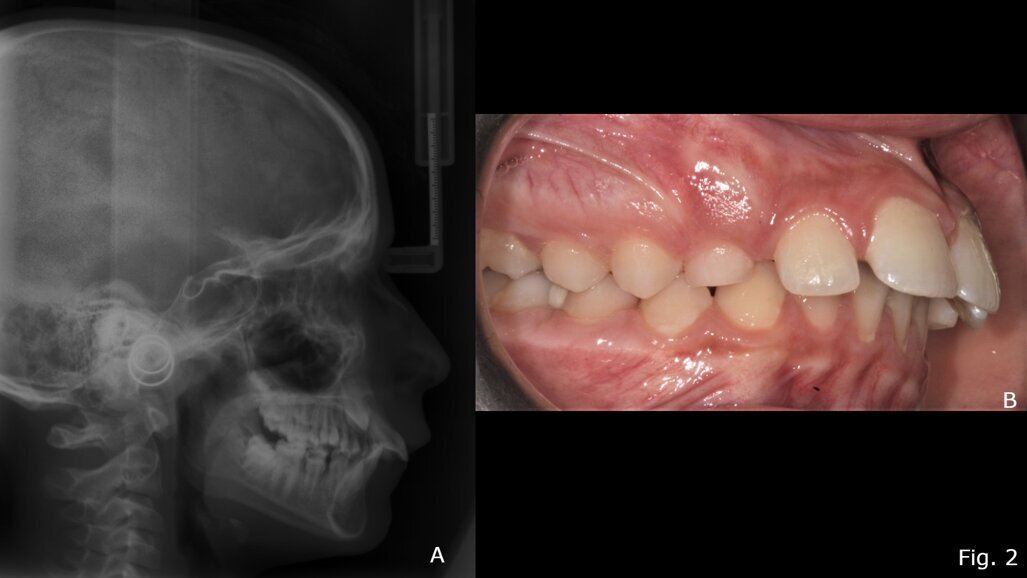

Il TB è uno dei dispositivi più comunemente usati per ottenere la correzione funzionale della malocclusione scheletrica di classe II18, 19. Provoca una riduzione statisticamente significativa dell'angolo ANB, riducendo l’OVJ e migliorando l’indice di Wits15. Il dispositivo, infatti, promuove il rimodellamento del condilo nella posizione avanzata inducendo un significativo aumento della lunghezza della mandibola (Co-Gn in mm)15, 18. Il rimodellamento adattivo può verificarsi su entrambe le superfici dell'articolazione temporo-mandibolare per migliorare la posizione della mandibola in relazione al mascellare superiore17. Un altro vantaggio è il controllo della dimensione verticale. Infatti, con il trattamento TB, lo sviluppo verticale si ottiene scartando gradualmente i blocchi in resina della placca, favorendo l'estrusione dei denti posteriori e livellando il piano occlusale20-22. Sul piano trasversale, l’utilizzo del TB ha effetti prevalentemente dentali rispetto a quelli scheletrici13. Uno degli svantaggi principali dell'apparecchio TB è che la correzione dell'overjet è data anche da cambiamenti dentoalveolari (60%) come la proclinazione degli incisivi inferiori23. Vari autori hanno proposto modifiche all'apparecchio TB per aggirare questo effetto indesiderato24-26. Ad esempio, l'uso contestuale dell'ancoraggio con mini-viti può fornire un controllo assoluto sulla posizione degli incisivi inferiori, aumentando così la correzione ortopedica nella terapia miofunzionale di classe II27. TB sembra essere particolarmente efficace nei casi di II classe in cui prevale la componente di ipoplasia mandibolare15, 28 (Figg. 2, 3).

Fig. 2 - Teleradiografia latero-laterale pre-trattamento con Twin-Block (A); Foto occlusale destra pre-trattamento (B).